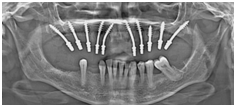

The disadvantages of a cantilever bridge were, also, explained to the patient.20 Due to certain constraints, the patient chose to delay the treatment in the lower arch. On the day of the surgery, the remaining teeth in the maxillary arch were extracted under local anesthesia while the placement of 10 smooth-surfaced implants (Strategic Implant®, Simpladent GmbH, Implant type BECES) was done based on the principle of cortical engagement. Pterygoid plates, floor of the maxillary sinus and nasal floor were the cortical bones engaged. The placement in the anterior region was oblique (Figure 2) in order to achieve a better emergence profile and greater prosthetic freedom. Impressions were made according to the manufacturer's instructions using impressions caps and addition silicone material. Laboratory analogs were placed in these impression caps to create a laboratory model. Parallelism of the implant was achieved by bending of the implants during surgery and use of the guiding jig provided by the laboratory technician. A jaw relation was taken in a conventional method using aluminium reinforced bite registration wax.

Figure 2 Orthopantomograph (OPG) of the patient revealing placement of 10 smooth-surfaced implants with oblique placement in anterior region based on the principle of cortical engagement.

Trial of the metal framework was done on the second day. Zig placement guided the operator to eliminate interferences by selective grinding of the implants observed by the technician on the model to facilitate proper placement of the metal framework. After confirming proper placement of the metal framework, registration of jaw relation was done using aluminium reinforced bite registration wax to confirm and improve on to the previously registered jaw relation. A cantilever bridge was designed in the mandible to have equal length of the occlusal table. Avoidance of unilateral chewing which is an important aspect in the philosophy of cortical implantology was taken care of.21 The final porcelain-fused-to-metal (PFM) bridge (Figures 3a&3b) was cemented on the third day. The occlusal scheme was given according the one described by Ihde S and Ihde AA.21 The patient was instructed about the importance of bilateral mastication and periodic follow-ups. The follow-up of the case showed stable gingival condition and marked improvement in the consistency and function of gingival tissues (Figurea 4a&4b) which showed a noticeable healing. Some amount of expected gingival recession was seen in the posterior regions where implants were placed in the extraction sites. One year follow-up of the patient showed a stable implant engagement with no cortical radiolucency around the threads of the implants (Figure 5).